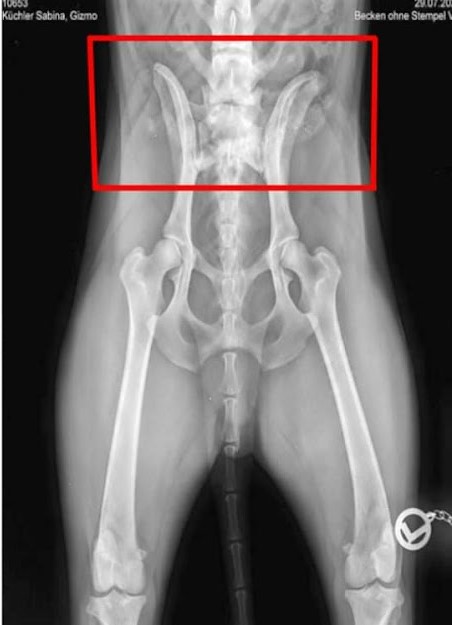

Hier nun noch die beiden Röngten von Gizmo wo der Übergangswirbel zu sehen sei, wo mich hier besonders interessiert, ob ihr den zum Einen auch seht und zum Anderen, welche Stufe von Übergangswirbel das wohl ist - 0 bis 3?

Beim Betrachten des Bildes wurde unser Tierarzt aber stutzig. Er zählte und zählt mehrmals und fand dann raus, dass Gizmo einen Übergangswirbel hatte.

Da das eine Erkrankung ist die bei Schäferhunden vorkommt hoffe ich, dass ich hier Tipps bekommen werde.